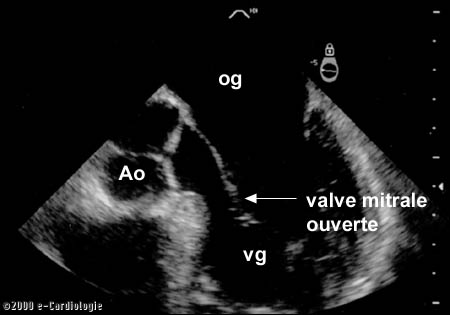

L’échographie-doppler du cœur par voie trans-oesophagienne permet de visualiser parfaitement le cœur.

La mobilité du muscle du cœur et des valves peut être parfaitement visualisée. Les membranes entre les oreillettes, les ventricules sont également très bien vues.

Les flux sont particulièrement bien enregistrés au niveau des différentes valves et à l’arrivée des veines. Le cardiologue peut également très bien visualiser l’aorte descendante localisée dans la poitrine et une petite partie de l’abdomen.

vg: ventricule gauche, vd: ventricule droit,

og: oreillette gauche, od: oreillette droite, Ao: aorte.